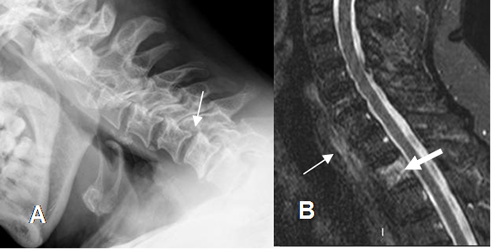

Fig 167. Aumento del espacio interespinoso.

A: Rx lateral y B: TAC reconstrucción sagital. Aumento del espacio entre las apófisis espinosas de C2 y C3, por anterolistesis post-trauma.

Fig 175. Lesión ligamentaria.

A: Rx lateral en flexión. Leve anterolistesis GI de C6, sobre C7.

B: RM sagital en STIR. Contusión del cuerpo vertebral, sin pérdida de altura. (Flecha gruesa). Hay cambios inflamatorios en los tejidos blandos prevertebrales (Flecha delgada), por esguince GI-II.